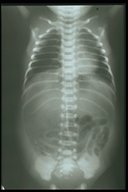

Free air under the dome of right diaphragm indicates that there is bowel perforation

Large gas shadow at the central abdomen in the supine film and the well outlined falciform ligament (white line) indicates bowel perforation